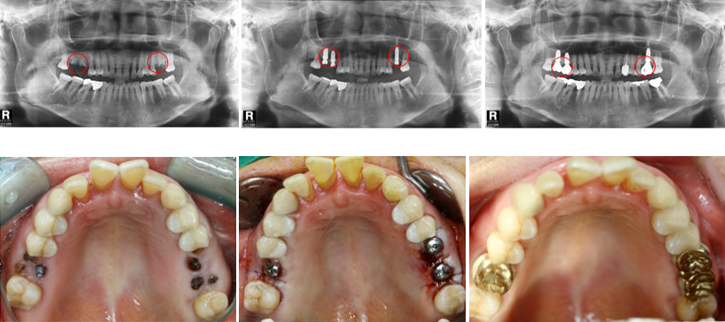

우선 CT촬영 등을 통해 구강상태를 정밀 진단 후 환자의 상태에 따라 맞는 치료 계획을 세웁니다. 구체적인 임플란트 시술 과정과 기간은 환자의 상태에 따라 달라질 수 있다고 해요.

2단계 1차 수술

이 과정은 픽스쳐를 잇몸뼈에 심는 과정인데요. (픽스쳐란 치아의 뿌리 역할을 하는 것을 말함)

이때 잇몸을 절개하는 방식과 무절개 방식 두가지가 있다고 해요.

잇몸 절개 방식은 일반적으로 많이 시술하며 잇몸을 열어 치조골에 필스쳐를 심은 뒤 절개 부위를 덮고 실로 봉합하는 방식인데요. 이 수술은 보통 1시간 정도 걸리며 수술후 1~2주뒤 수술부위가 아물면 실밥을 제거한다고 해요.

무절개 방식은 작은 구멍을 내어 고정체를 심는다고 해요. 잇몸 절개와 봉합과정이 없어 비교적 시술이 간단하고 회복기간도 빠르지만 잇몸과 잇몸뼈가 건강해야 가능한 시술이라고 해요. (뼈이식을 해야하는 경우에는 불가하다고 해요)

3단계 2차 수술

픽스쳐와 보철물을 견결할 공간을 만들기 위해 진행하는 수술로 잇몸밖으로 나사를 연결하는 과정인데요. 1차 수술 이후 식립한 임플란트 픽스쳐가 자연 치아의 뿌리처럼 잇몸뼈에 단단하게 고정될 때까지 기다려야하며 픽스쳐가 치조골과 단단히 결합해 안정화되어야 2차 수술을 진행할 수 있다고 해요.

그후 연결기둥인 임플란트 지대주를 부착한다고 해요.

4단계 크라운제작 및 교정

수술부위가 아물면 임플란트 지주대와 주변치아를 본을 뜬뒤, 치아 형태의 보철물인 크라운 제작을 한다고 해요. 크라운 제작 기간은 보통 일주일 정도라고 해요. 보철물이 완성되면 크라운을 임플란트 지대주에 장착해 고정시킵니다고 해요. 그 다음 음식을 씹을 때 불편함이 없도록 조정한다고 해요.

임플란트 시술과정과 시술기간은 환자의 구강 및 건강 상태에 따라 달라질 수 있다고 해요.